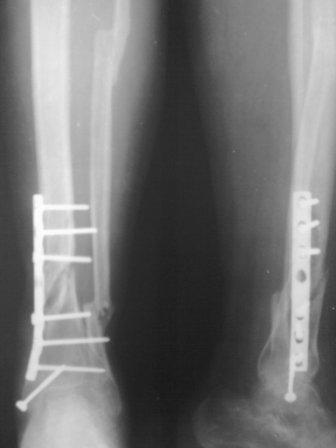

Остеомиелит и дефект голени

Мужчина 56 лет, оперирован 14 мес. назад в одном обл.центре, до сих пор лечился консервативно у леч. врача всяким мазями.

Локально на снимке явного гнойного выделения нет, незначительное сукровичное, не болит, нога неопорная.

Сегодня госпитализировал, предварительный план: удаление пластины, дебридмент, если смогу то VAC, и остеосинтез аппаратом Илизарова, последующим можно ли закрыть суралным лоскутом?

Или предлагаете другие варианты? времени мало, больной находиться на платной койке (из другой обл.)